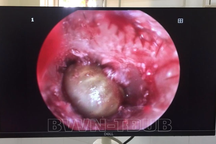

Để xử trí cho bệnh nhân, các bác sĩ đã tiến hành gây mê và lấy thành công dị vật là củ cà rốt có đường kính khoảng 4cm, dài 20 cm.

Củ cà rốt dài 20cm sau khi lấy ra khỏi cơ thể bệnh nhân (Ảnh: Bệnh viện cung cấp).